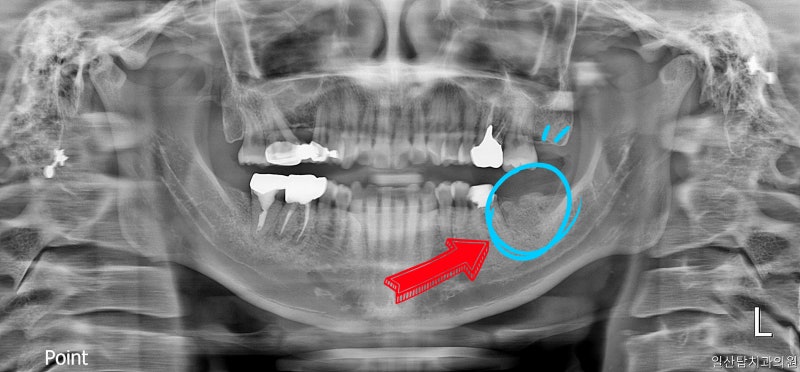

▲ 시술 전 파노라마

▲ 치료 후 파노라마 사진 설명 없이 비포 애프터 사진만 봐도 치과 치료를 많이 하셨고 임플란트가 필요한 치아가 많다는 것을 확인할 수 있습니다. 만성치주염이란 치아를 둘러싸고 있는 조직에 염증이 생겨 치아를 지탱하는 잇몸과 뼈가 파괴되는 질환입니다. 이러한 만성 치주염의 원인은 세균과 음식물 찌꺼기(박테리아 플라크, 세균 플라크)가 칼슘과 결합하여 치아가 나면서 치석을 형성하고 치주낭을 형성하며 치조골을 파괴하여 잇몸 질환의 증상을 유발하기 때문입니다. 습관은 물론 전신질환과 불균형, 당뇨, 심혈관질환, 임신, 영양이상 등도 원인이 될 수 있습니다. ▲ 발치 후 뼈이식이 필요할 때! 다양한 이유로 발치를 해야 하는 경우도 있고, 뼈이식을 해야 하는 경우도 있고, 발치가 필요하지 않은 경우도 있습니다. 치과용 임플란트를 식립하기 위해서는 식립된 치은의 상태, 즉 주변 조직에 남아있는 뼈의 양이 임플란트의 직경과 높이를 고려하여 치은골의 폭과 길이가 충분히 확보되어야 합니다. 치아의 경우 더 많은 뼈 이식이 필요합니다. ▲ 발치 후 뼈이식이 이렇게 염증이 심한 상태가 되면 염증이 치아뿐만 아니라 주변 치아까지 번지게 됩니다. 골이식은 멸균 후 비감염성으로 진행하였으며, 골이식은 물방울 레이저로 진행하였다. ▲ 물방울 레이저 골이식 물방울 레이저는 잇몸 주변 조직에 대한 살균 효과가 뛰어나 시술 시 출혈이 거의 없고 시술 후 부기가 거의 없다. 레이저에 비해 큰 이점을 제공하는 고가의 의료 기기입니다. 치료가 잘 되었습니다. 염증이 심한 잇몸을 무통 레이저로 치료한 사례! 안녕하세요 파주운정 아픈치과의원입니다. 파주운정 안아픈치과의원 일산탑치과 원장입니다. 치과에서 레이저 치료? 궁금하신 분들을 위해… blog.naver.com 골이식 유합술은 부족한 부분을 골이식재로 보강한 후 보통 3~5개월이 소요됩니다. ), 임플란트 고정물을 배치합니다. ▲ 임플란트 픽스쳐 식립 임플란트 식립이 불합리한 경우 픽스쳐, 즉 임플란트의 고정체가 제대로 고정되지 않아 시간과 비용이 더 많이 들 수 있다. 따라서 다음 치료를 진행하기 전에 충분한 치조골을 준비하는 것이 중요합니다. ▲ 임플란트 식립 5개월 후 모습 임플란트 식립 후 치은골과 픽스츄어가 잘 결합되기까지 시간이 걸립니다. 이 환자를 예로 들면 약 5개월이 소요되며 임플란트 고정값은 다음 값을 사용하여 계산되며 수치로 표시됩니다. ▲ ISQ 임플란트 안정성 견적을 측정할 때 70 이상의 값을 얻으면 치유가 제거되고 수복물이 위에 놓일 수 있습니다. Torque 측정법이 있지만 이 방법들은 정확하지 않고 식립된 인공치아에 악영향을 끼친다 ▲ 보철물이 완성된 후 이렇게 보철물을 들어올리면 성공적으로 임플란트 치료가 끝난다. 그러나 한 가지 기억해야 할 것이 있습니다. 수술 후 관리가 중요합니다. 임플란트 자체에는 신경이 없기 때문에 통증을 느끼지 못할 수도 있지만, 임플란트 주위나 치아와 임플란트 사이의 공간에 플라그가 침착되어 잇몸에 염증이 생겨 임플란트 주위염을 유발할 수 있습니다. 이 점은 매우 중요합니다! 임플란트에 염증이 생길까요? 임플란트주위염 일산서구치과의원 안녕하세요. 일산서구치과병원 일산탑치과병원 원장입니다. 임플란트는 상실된 치아를 대신할 수 있는 좋은 치료법… blog.naver.com 임플란트 주변에 염증이 생겨도 스스로 치유되지 않아 자각하기 쉽고 치아를 보호하는 치주인대가 없기 때문에 더욱 주의가 필요합니다. 치아 조심해서 다루십시오. 또한 임플란트를 식립한 치과의사가 정기적으로 체크인하는 것을 기억하는 것이 중요합니다.물방울 레이저